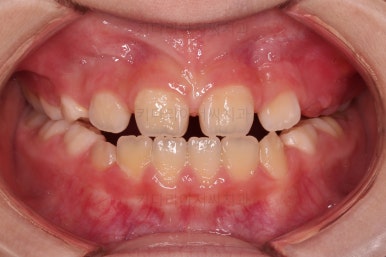

초진 시 입안의 모습입니다.

아래쪽 치열이 전반적으로 윗니보다 앞쪽에 위치한 전형적인 앵글씨 3급 부정교합인데요.

어금니에서부터 앞니까지 아랫니가 윗니보다 앞쪽에 위치하네요.

특히 앞니는 아랫니가 윗니보다 나와있는 "반대교합" 상태였고요.

또한 위아래로 겹침이 없고 떠있는 "개방교합" 상태였어요.

즉, 앵글씨 3급 부정교합 - 반대교합 - 개방교합 등 굉장히 복합적인 교합의 문제를 가진 환자였습니다.